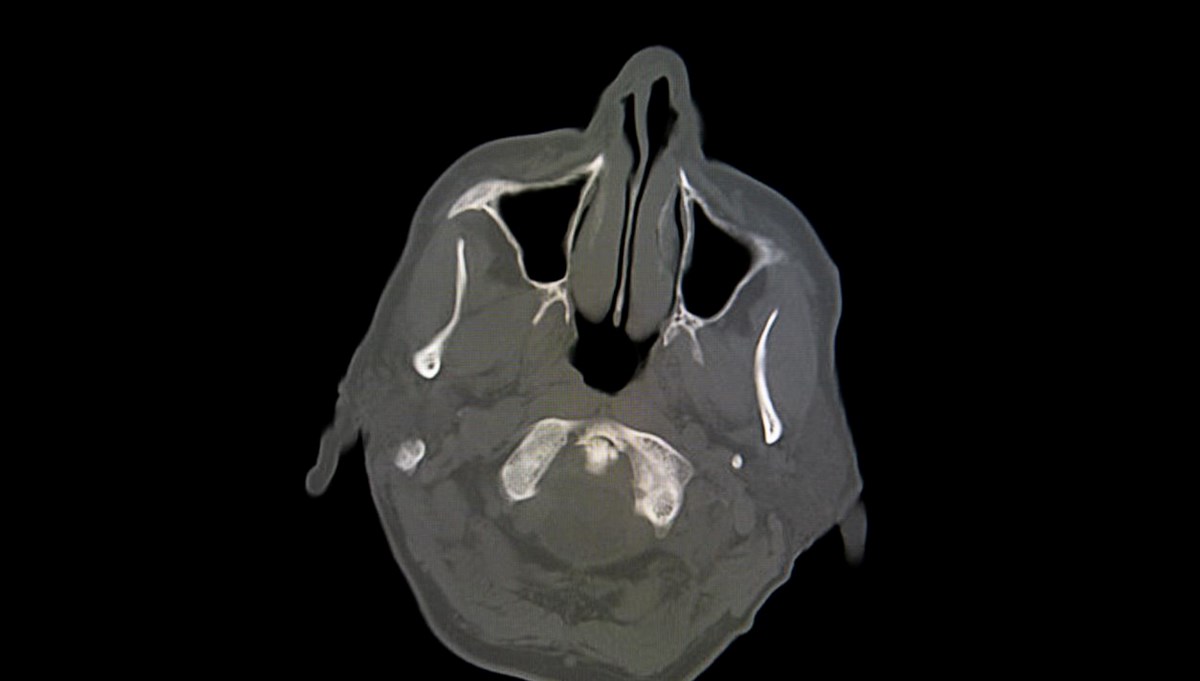

Bunlardan biri de Fransa’da yaşandı. O zamanlar 44 yaşında olan kimliği gizli adam, yaklaşık iki hafta boyunca bacağında hafif bir ağrı ve güçsüzlük fark edince ilk olarak doktora gitti. Beyin taraması sonrası adamın beyninin yarısının olmadığı, "Hidrosefali" adı verilen kafatasında ince bir beyin dokusu tabakası ve sıvı bulunduğu ortaya çıktı. Bilişsel psikolog Axel Cleeremans, adamın normal bir yaşam sürdüğünü, ailesinin olduğunu ve çalıştığını belirtti. Şikayeti sırasında yapılan IQ testinin sonucu 84 olarak belirlendi; bu, normal aralığın biraz altında. Doktorlar, hastalığının nedeninin beyninde biriken sıvı olduğunu ve bu durumun 30 yıl boyunca beyninin büyük kısmının tahrip olmasına yol açtığını düşünüyor. Öte yandan hastalık bebekken teşhis edilmiş ve stent takılmıştı. Ancak 14 yaşındayken stent çıkarıldığında, beyninin büyük bir kısmı aşınmaya başlamış. Geçmişte, bilincin belirli beyin bölgeleriyle bağlantılı olduğu düşünülüyordu; ancak bu tür hikayeler, bilincin yalnızca belirli bir bölge tarafından yönetilmediği fikrini savunan yeni teorilerin ortaya çıkmasına neden oldu.